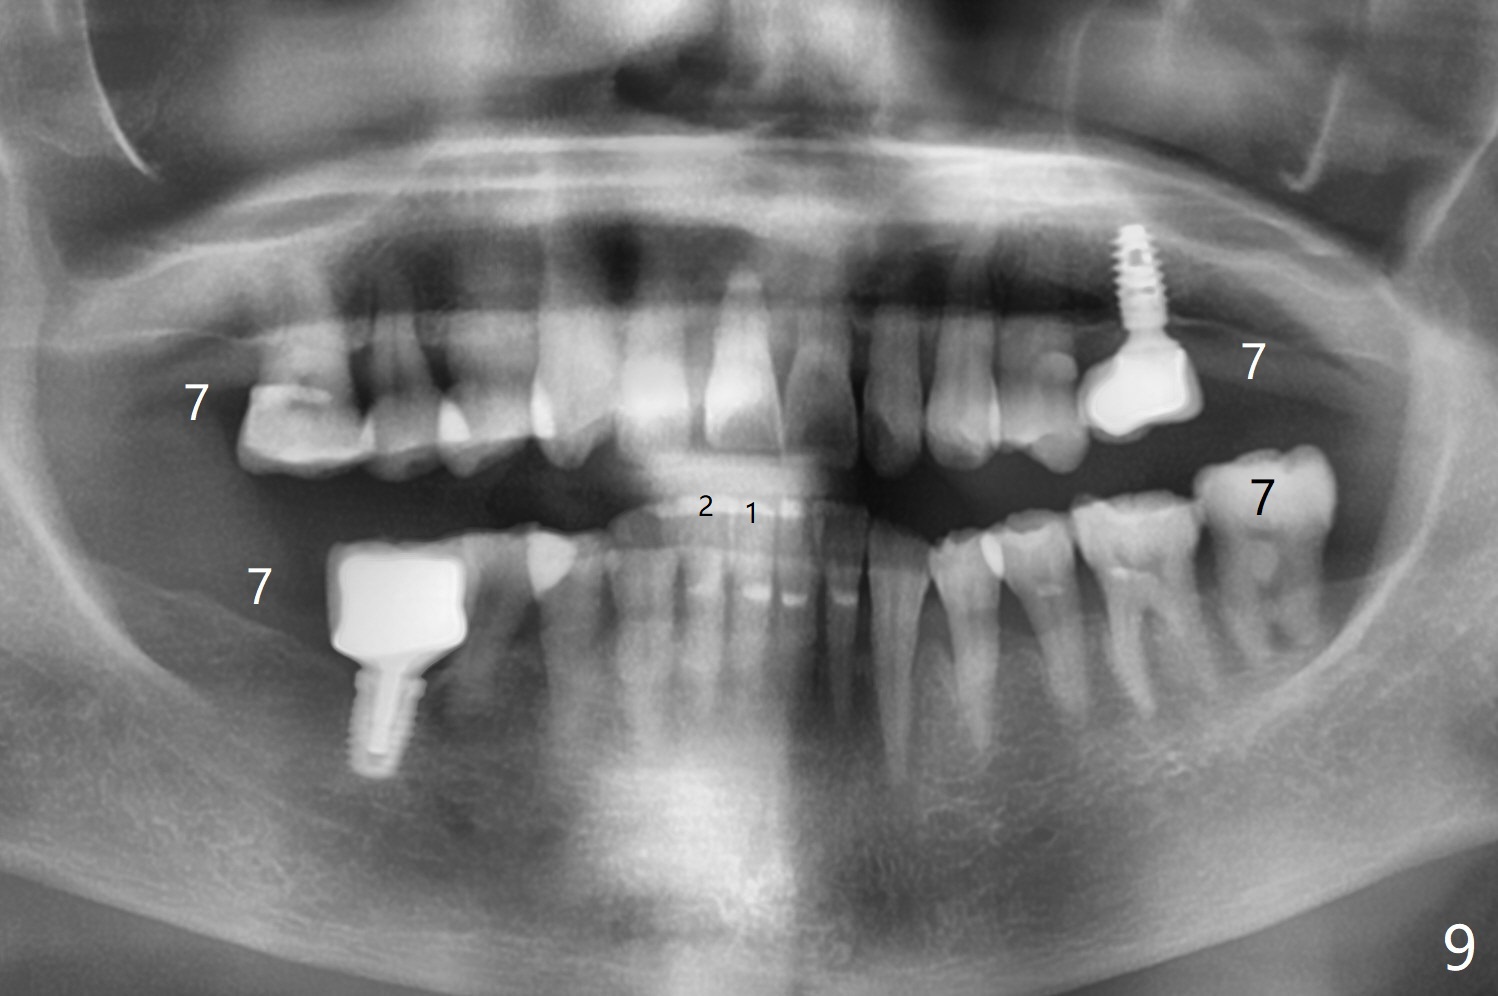

59岁女今天就诊,“上门牙快掉下来”,检查表明右上1延长(图一:长箭头),牙龈退缩(短箭头),红肿(*),颊侧骨板触诊不觉得塌陷(图二)。咬合时,患牙前移(图三),伸长的下切牙(图三,九:1,2)造成咬合创伤。因此拔牙前,将降低下门牙切缘(图四,五(黑色)),为临时牙冠创造足够修复空间。CT冠状切面显示颊侧(图六:B)骨板缺失,可以植入两段式植体(3.5x11.5 毫米),但是最细基台(4毫米直径,图七(粉红色和蓝色))显得太粗,不利于腭侧修复空间形成,而2.5x14(4)毫米一段式植体不仅创造更多颊侧植骨空间(图八(红箭头)),而且由于固有基台直径小(白箭头),容易形成腭侧修复空间。一旦前牙植体永久性修复完成,督促病人做三个第二磨牙植牙修复(图九:7),减少对前牙植牙创伤。临时牙冠不仅解决美观问题,而且固定骨粉,保持颊侧骨板隆起,维持牙龈缘和乳头。在大多数情况下,使用现成树脂牙冠(crown form)制作临时修复物,这个病例牙齿完整,截除的牙冠可以用来做临时牙冠。